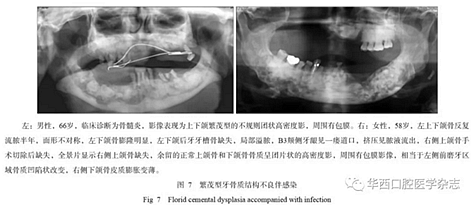

牙骨質(zhì)結(jié)構(gòu)不良具有多樣性的影像學特征,所以在臨床上也表現(xiàn)為不同的癥狀,由于該疾病生長比較緩慢,患者在未出現(xiàn)癥狀前經(jīng)常不會來就診。當患者出現(xiàn)癥狀時或者醫(yī)生偶然在拍攝片子后發(fā)現(xiàn)根尖暗影,就會遇到診斷的問題,最常造成診斷不清的是診斷為慢性根尖周炎,按照慣性思維往往首先思考根尖周炎,就采用傳統(tǒng)的根管治療方式進行治療,但治療以后發(fā)現(xiàn)根尖的骨質(zhì)改變更加明顯,極端的甚至出現(xiàn)長時間的癥狀不消失或者不愈,或者形成骨髓炎改變。多發(fā)性或者泛發(fā)性的牙骨質(zhì)結(jié)構(gòu)不良常常造成牙脫落或者拔牙后出現(xiàn)感染,進而出現(xiàn)骨髓炎改變,頜骨骨皮質(zhì)密度增高、增厚,為炎性反應(yīng)性增生所致(圖7)。